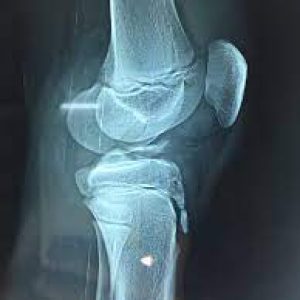

- Preoperative Assessment: Comprehensive evaluation, including physical examination, imaging studies (X-rays, MRI), and assessment of knee stability and function.